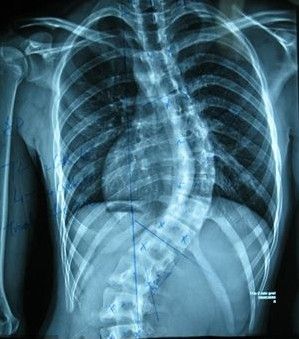

强直性脊柱炎会有的症状表现是哪些

第一、僵硬感觉,这种现象在患者早上起床的时候是比较明显的,活动之后会有所减轻,这也是该病发展的一种表现,更是该病较常见的症状,患者在早上起床时或者久坐站起时等等,这时候腰骶部位就会感觉到有僵硬和活动上的不利,只有借助外力才能减轻,因此对有这种现象的人,要及时的到医院进行咨询,然后让医师帮我们解决这种现象,这样才能防止病情发展。

第二、腰背的疼痛,这也是比较常见的一种表现,患者疼痛的部位一般都在腰部以下,要知道该病会造成主要关节的病变。而且影响较厉害的就是腰椎处的关节,刚开始的时候,患者只是有轻微的隐痛或者不适,但是患者会越来越感受到病情的严重性,造成活动上的不便或者功能的丧失等等,这些都是患者必须要重视的。只有这样才能尽快减轻疼痛。

第三、连接点的疼痛,这里所讲的连接点主要是指肌腱和韧带处的附着点,所产生的疼痛主要是因为一些非细菌性质的炎症。这种炎症会造成患者出现疼痛和肿胀的现象,这样一来就会造成活动上的不灵活,慢慢的就会完全失去较基本的功能,这对患者来讲是非常痛苦的,也是令患者丧失治疗信心的原因,所以说要尽快找方法解决这种表现。